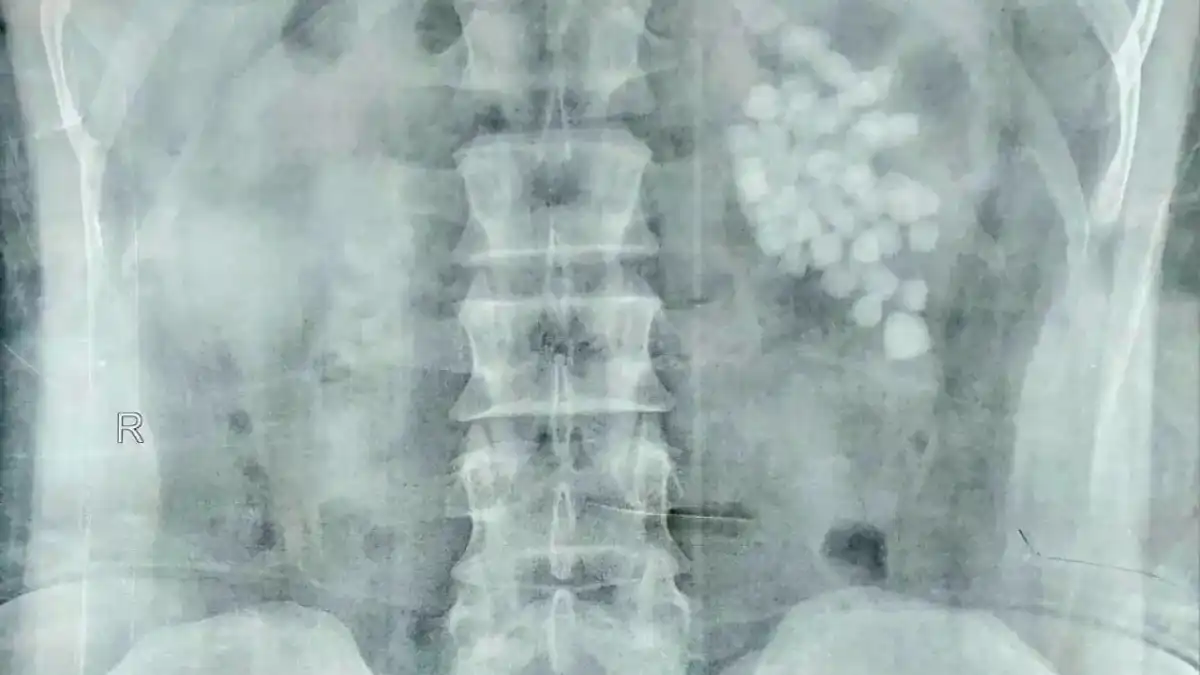

وكشفت الفحوصات والأشعة عن وجود كمية كبيرة من الحصوات المتجمعة داخل حوض الكلية اليسرى، الأمر الذي تطلّب تدخلًا جراحيًا عاجلًا لتفادي مضاعفات خطيرة، من بينها انسداد مجرى البول أو تدهور وظائف الكلى.

ودخل المريض العملية تحت التخدير العام، ليبدأ الفريق الطبي باستخدام تقنية منظار الكلية عبر الجلد (PCNL)، وهي إحدى أحدث تقنيات جراحات المسالك البولية، حيث تسمح بإزالة الحصوات عبر فتحة لا تتجاوز سنتيمترًا واحدًا.

وجرى تفتيت الحصوات باستخدام مزيج من تقنيات التفتيت الهوائي والليزر، وفقًا لطبيعة وحجم كل حصوة، لضمان تنظيف الكلية بالكامل دون الإضرار بأنسجتها.